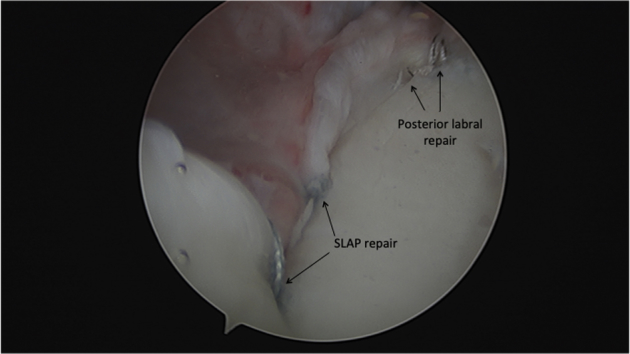

Repair of the Posterior Labrum

With a view from the anterior portal, the posterior inferior labral tear is identified. The labrum is probed and mobilized with an elevator through the posterior portal. A 45° curve right ReelPass is then used to pass suture around the labrum at the 5:30 position, a racking hitch suture is placed, a pilot hole is drilled, and a posterolateral anchor is impacted. These steps are repeated for the sixth and final anchor in the 4:30 position (Fig 7).

Fig 7.

Arthroscopic image of the left glenohumeral joint viewing from the anterior portal with the patient in a right modified lateral decubitus position. The SLAP repair is visualized with knotless suture anchors at 1 o’clock and 2 o’clock, as well as the posteroinferior labral repair with suture anchors at the 4:30 and 5:30 positions. Note the labrum is anatomically reduced at each point of fixation.